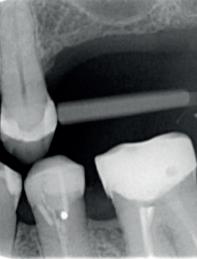

Een 48-jarige gezonde vrouw presenteerde zich in de nazorgfase 2 jaar na initiële behandeling met pockets van 6–7 mm en furcatieproblematiek bij de 47 en 46 (afbeelding 1.1 en 1.3). Bloeding bij sonderen was aanwezig, maar de patiente wilde geen chirurgische behandeling. Ze hield er een keurige mondhygiëne op na en kwam trouw iedere drie maanden voor nazorg.

De pockets werden onder lokale anaesthesie behandeld met een combinatie van ultrasoon en handinstrumentarium volgens de hierboven beschreven methode. De natriumhypochloriet/aminozuur-gel werd vijfmaal aangebracht en na iedere applicatie mechanisch verwijderd. Daarna werd de pocket gevuld met cross-linked hyaluronzuur.

Na 6 maanden was de pocketdiepte teruggebracht tot 3 mm en was er geen bloeding na sonderen waarneembaar. Een recessie van 2 mm was aanwezig. Röntgenologisch was er nieuw bot zichtbaar (afbeelding 1.2 en 1.4).